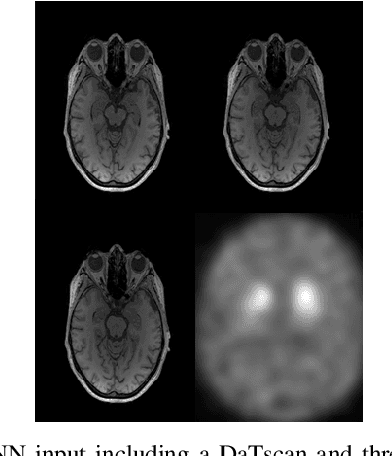

Abstract:The paper presents a novel approach, based on deep learning, for diagnosis of Parkinson's disease through medical imaging. The approach includes analysis and use of the knowledge extracted by Deep Convolutional and Recurrent Neural Networks (DNNs) when trained with medical images, such as Magnetic Resonance Images and DaTscans. Internal representations of the trained DNNs constitute the extracted knowledge which is used in a transfer learning and domain adaptation manner, so as to create a unified framework for prediction of Parkinson's across different medical environments. A large experimental study is presented illustrating the ability of the proposed approach to effectively predict Parkinson's, using different medical image sets from real environments.